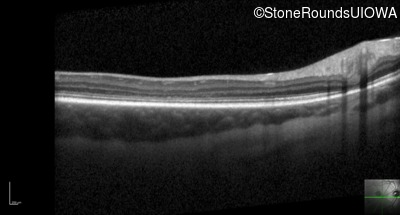

Optical Coherence Tomography - Right - 20/80 -1

Exemplar / OCT Stack